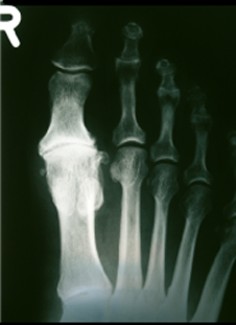

Alluce valgo

- Da scarpe troppo strette

- Quasi sempre bilaterale

- Limitazione del movimento della base dell'alluce

- Osteofite mediale, con borsite e spesso con infiammazione cronica

- Posizione secondaria in valgo delle dita II e III, in casi seri l'alluce si posiziona sotto il dito II, rare volte sopra

- Dolori soggettivi non proporzionali al valgo